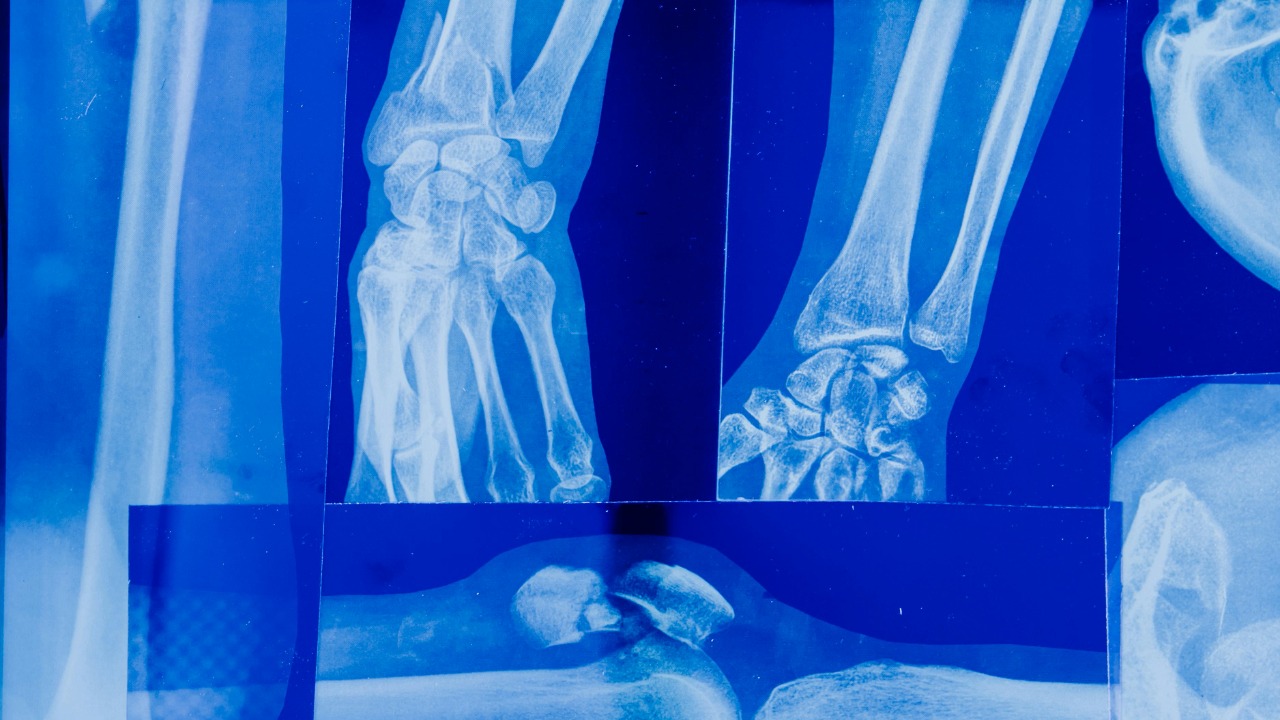

New breakthrough may let bones get workout benefits without moving

Read More: New breakthrough may let bones get workout benefits without movingScientists are closing in on a goal that once sounded like science fiction: triggering the benefits of a workout inside…